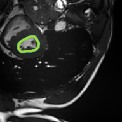

Despite their outstanding accuracy, semi-supervised segmentation methods based on deep neural networks can still yield predictions that are considered anatomically impossible by clinicians, for instance, containing holes or disconnected regions. To solve this problem, we present a Context-aware Virtual Adversarial Training (CaVAT) method for generating anatomically plausible segmentation. Unlike approaches focusing solely on accuracy, our method also considers complex topological constraints like connectivity which cannot be easily modeled in a differentiable loss function. We use adversarial training to generate examples violating the constraints, so the network can learn to avoid making such incorrect predictions on new examples, and employ the Reinforce algorithm to handle non-differentiable segmentation constraints. The proposed method offers a generic and efficient way to add any constraint on top of any segmentation network. Experiments on two clinically-relevant datasets show our method to produce segmentations that are both accurate and anatomically-plausible in terms of region connectivity.